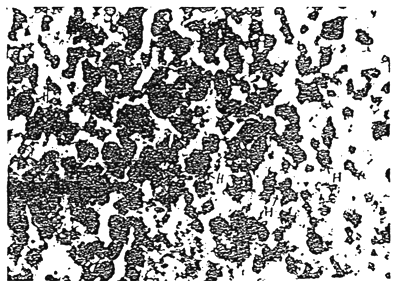

There was heavy deposition of haemosiderin pigments in the liver sections of catla and silver carp suffering from dropsy as shown in fig. 2 and 3. The pigment deposition was so profuse that the normal cellular architecture of the liver was damaged. The chordal arrangement of the liver cells was completely obliterated. The ovary of a few healthy looking catla from reservoir I was also collected along with the sick specimens and it was observed that pathological haemosidesis was present in the ovary of the healthy specimen too. This indicated a probable link between poor gonadal maturity condition of catla in this pond and of the pigment deposition as well as vascular pathology.

Figure 2. Photomicrograph of the liver section of catla suffering from dropsy showing deposition of Haemosiderin (H) pigment under perl's prussian blue stain.

Figure 3. Photomicrograph of the liver section of Silver carp suffering from dropsy showing deposition of Haemosiderin (H) pigment under perl's prussian blue stain.